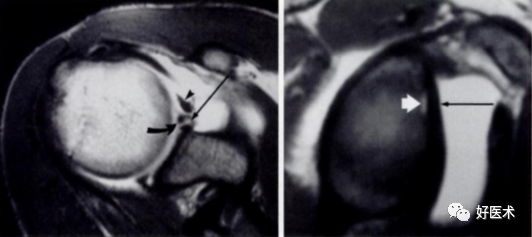

3)完全性撕裂

原发征象:肌腱局部缺如,连续性液体信号横贯肌腱的全层,这使得盂肱关节和肩峰下滑囊相通。

继发征象:

①肩峰下滑膜囊积液,积液在T1WI /PDWI上呈中等信号,T2WI+FS上呈高信号;

②冈上肌肌肉、肌腱结合处回缩(正常位置在肱骨头上方);

③滑囊旁脂肪垫的渗出丢失。

MR 关节造影:局限性或弥漫性充满造影剂的裂隙贯穿肌腱全层,肌腱失去其连续性。